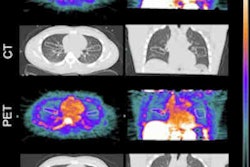

The three professional groups recommend the reporting of coronary artery calcification (CAC) when imaged on all CT scans and offer guidance on how to categorize the severity of CAC by patient.

"Furthermore, we recommend that reports include recommendations for subsequent management, namely the assessment of modifiable cardiovascular risk factors and, if the patient has chest pain, assessment as per standard guidelines," wrote a team led by Dr. Michelle Williams, PhD, of the University of Edinburgh in the statement posted on 29 October.